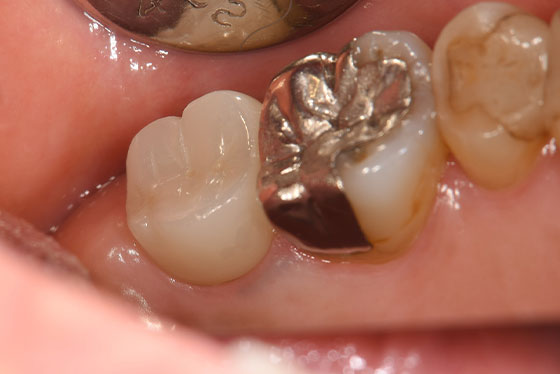

以下、他院で「抜歯」と言われた歯を残したケースになります。

他院で「歯の根が割れてるので、抜歯になります」と言われた場合でも、実際は割れておらず、通常の根管治療で対応ができる場合があります。